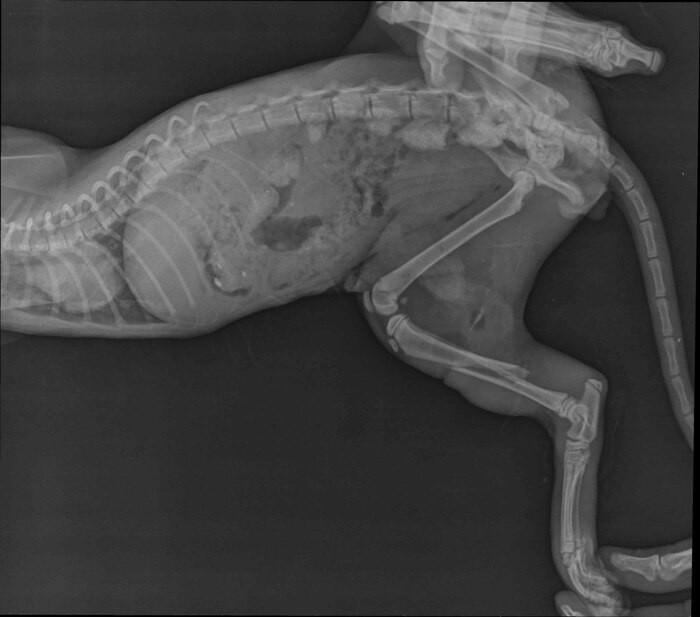

Когда его наконец привезли в клинику, стало ясно: это не “царапинка”. Не “ссадина и пройдёт”.

У Облачка перелом, огромная рваная рана и вспорот живот.